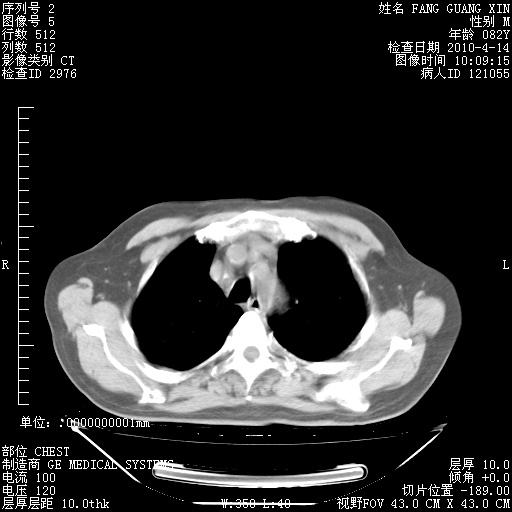

4月14日肺部CT

23.JPG

24.JPG

25.JPG

26.JPG